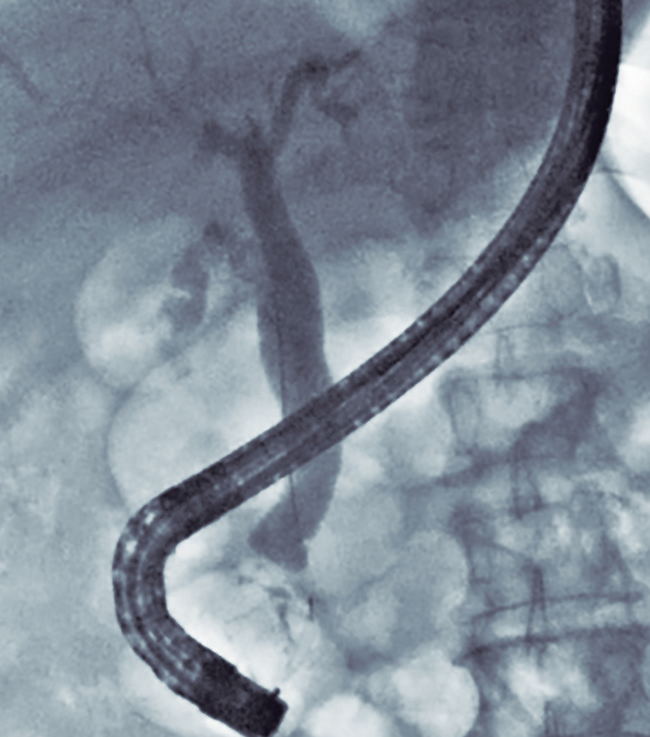

Por la edad del paciente, el hallazgo de los DDP y la dilatación del conducto pancreático principal, se decidió complementar el estudio diagnóstico con la realización de una ultrasonografía endoscópica (USE) biliopancreática, para descartar la presencia de neoplasias pancreatobiliares no evidenciadas en los estudios previos de imágenes. La USE biliopancreática mostró la presencia de un DDP de gran tamaño, dilatación coledociana y escaso barro en la vesícula biliar. El páncreas no presentaba alteraciones y el conducto pancreático principal no se encontraba dilatado. Con los hallazgos descritos, se descartó la presencia de coledocolitiasis y neoplasias pancreatobiliares, y se postuló como hipótesis diagnóstica el síndrome de Lemmel. El tratamiento elegido fue la realización de CPRE más esfinterotomía biliar, dada su baja tasa de morbimortalidad y la alta probabilidad de éxito, sobre la base de los reportes de casos previos. El paciente fue sometido a una nueva CPRE, en la cual se retiró la prótesis biliar (Figuras 4 y 5). La colangiografía mostró dilatación del colédoco (Figura 6), sin evidencia de litiasis. Se realizó el pasaje del balón extractor de vía biliar sin evidenciarse salida de litos ni barro biliar al retirarse este. Posteriormente, se amplió el acceso a la vía biliar mediante esfinterotomía, siendo adecuados el drenaje de bilis y el contraste. El hallazgo de barro en la vesícula biliar fue resuelto mediante colecistectomía laparoscópica. El paciente fue dado de alta sin molestias y el control de la analítica sanguínea fue normal. Tras seis meses de seguimiento, el paciente aún permanece asintomático.